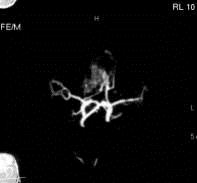

问题 病历摘要:??患者男性,56岁,因右侧视力下降伴视野缺损2个月来院就诊,诉头痛,无明显头晕,无视物重影,无恶心呕吐,无肢体抽搐,无肢体乏力,胃纳佳,大小便正常,既往史无特殊,入院检查:神志清楚,言语清楚,体毛分布正常,左侧视力4.6,右侧视力4.0,粗侧右颞侧视野缺损,左侧正常,颈软,四肢肌张力正常,肌力正常,病理征(-)。 大小为多少的动脉瘤称之为巨型动脉瘤?提示:该患者行全脑血管造影,诊断前交通巨型动脉瘤并部分血栓形成。

选项 A.≥10mm B.≥15mm C.≥20mm D.≥25mm E.≥30mm F.≥40mm

答案 D